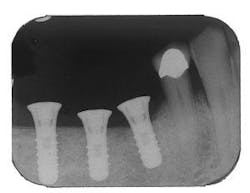

Figure 5 - Placement of three ITI implants

Figure 9 - ITI implant placement Tooth No. 3

Figure 10 - Restored implants